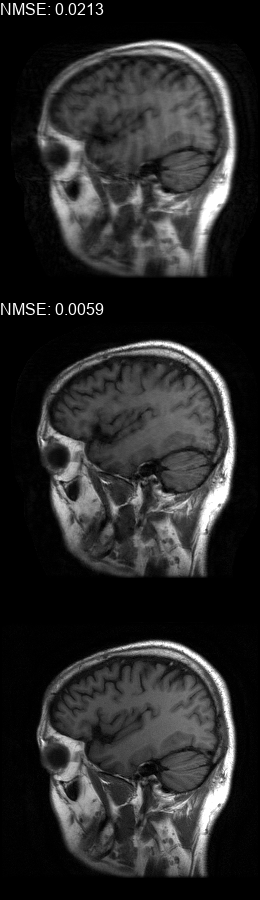

Results  Experimental results using the two presented datasets, for the fully-sampled and under-sampled k𝑘k-space scan orders, are shown in Table 1. The table presents the Normalized Mean Square Error (NMSE) obtained for each of the scan orders. For the Transaxial dataset, we only show the results for the challenging task where the DP contains only up to 707070 columns of k𝑘k-space data. All methods are able to reduce the NMSE of the corrupted scans, however the methods that incorporate the DC layer achieve a much better result. These results match our subjective visual impression of the motion-corrected images, as may be seen in Fig. 3 for simulated motion in a fully-sampled k𝑘k-space data, and Fig. 4 for an under-sampled k𝑘k-space data.

Figure 3: Motion corrected images from the Diverse dataset calculated using the 𝒮260subscript𝒮260\mathcal{FS}_{260} scan order presented in Fig. 1b. The bottom row shows the motion-free image. The top row shows the motion-corrupted images. The middle row shows the corrected images calculated using our method. (a) contains a motion at t1=87subscript𝑡187t_{1}=87, (b) contains two motions at t1=46subscript𝑡146t_{1}\!=\!46, t2=170subscript𝑡2170t_{2}\!=\!170, (c) contains three motions at t1=72subscript𝑡172t_{1}\!=\!72, t2=227subscript𝑡2227t_{2}\!=\!227, t3=248subscript𝑡3248t_{3}\!=\!248, (d) contains two motions at t1=112subscript𝑡1112t_{1}\!=\!112, t2=216subscript𝑡2216t_{2}\!=\!216, (e) contains a motion at t1=66subscript𝑡166t_{1}\!=\!66, (f) contains three motions at t1=65subscript𝑡165t_{1}=65, t2=135subscript𝑡2135t_{2}\!=\!135, t3=159subscript𝑡3159t_{3}\!=\!159.